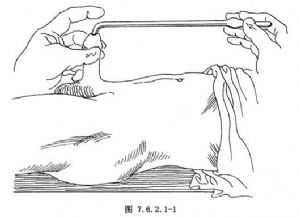

12.1 1.探子插入尿道

若病人爲平臥位,術者立於病人左側(右側亦可,視檢查者習慣);若病人爲截石位,術者可立於病人兩大腿之間。術者以右手拇、示、中三指握探子柄,探子塗以無菌潤滑劑。左手扶持病人的陰莖,使其向上伸直,用拇指及中指分開並固定尿道外口,將探子徐徐插入尿道口內(圖7.6.2.1-1)。